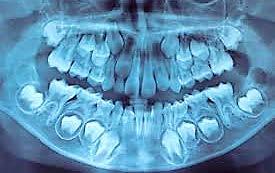

a. Observar radiográficamente las características anatómicas y dimensionales de los caninos superiores e inferiores respecto a dientes adyacentes (Figura 11).

b. Identificar radiográficamente la posición en que se encuentra el canino, respecto a los dientes adyacentes (Figura 12).

A partir de los 8 años, se puede observar radiográficamente el inicio de la reabsorción del canino deciduo (Figura 17).

El seguimiento del trayecto canino con un estudio radiográfico postero anterior, lateral de cráneo y ortopantomográfico, a partir de la edad señalada anteriormente, también es una herramienta efectiva que permite obtener un diagnóstico inicial, donde podrá observarse si se ha iniciado la reabsorción radicular del canino deciduo e identificar qué

dirección o trayecto está tomando el canino permanente (Figura 18).

Power y Short afirman en su análisis, que si el ángulo resultante formado entre la línea vertical determinada por la espina nasal anterior y el eje longitudinal del canino sea mayor a 31°, el éxito del acomodo del canino en el arco dental es reservado (Camarena-Fonseca et al. ,2017) (Figura 19).

Ubicación del canino

Un método sencillo para obtener el diagnóstico de inclusión canina en proceso o declarada, cuando no se realizó un seguimiento desde una edad temprana, será utilizando como herramienta de diagnóstico inicial, una ortopantomografia, donde al trazar puntos, planos y líneas de referencia en estructuras dentocraneales y en el eje longitudinal del canino propiamente, podremos ubicar tridimensionalmente el sitio de inclusión en proceso de formación radicular (estadio del 6 al 9), o definitivo, cuando el ápice se ha cerrado (estadio 10 de Nolla) y el diente no erupcionó8 (Figura 20).

Así lo mencionan (Ericson y Kurol) (Etal Eur J Orthod. 1988; 10:283–95)4, en el que proponen una clasificación, utilizando como herramienta una ortopantomografía y la angulación del canino, usando planos, líneas de referencia y la determinación de sectores, ubicando a estos de la siguiente manera: